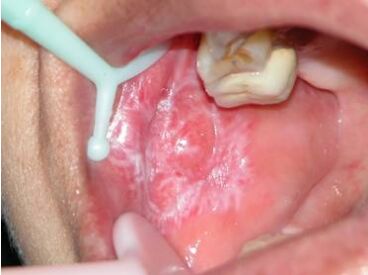

24.一位48歲的女性患者,有如圖所示的病灶來求診,她被其他醫師告知說可能是口腔癌。檢查時發現 在對側的頰黏膜也有類似的病灶,紗布並不能擦掉病灶,此病灶最可能的臨床診斷為何? (A)扁平苔癬(lichen planus) (B)上皮變異(epithelial dysplasia) (C)念珠菌病(candidiasis) (D)黏膜類天疱瘡(mucous membrane pemphigoid)